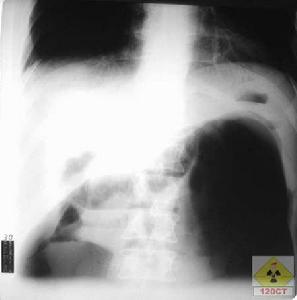

1.機械性腸梗阻 近端腸管內的氣體及液體重吸收和排出受到障礙腸管內細菌因腸內環境的改變產生大量氣體,而出現腹脹,B超鋇灌腸、X線立位照片或透視檢查可見小腸內有多個液平面及癟縮的結腸即可確診;

可做B超、鋇灌、腸X線立位照片或透視檢查見小腸內多個液平面及癟縮的結腸,可診為機械性腸梗阻;麻痹性腸梗阻可見結腸充氣擴張;見腸管漂浮在腹水中為腹腔積液特點。

1.常規放射科檢查。

(3)氣腹

氣腹是指腹腔內出現氣體而言。因為正常人腹腔不應存在任何氣體,所以一般說來氣腹均為病理狀態且大多為消化道穿孔所致。少部分為腹腔或腸道產氣菌的感染,除新生兒自然氣腹等極個別情況外一般氣腹患兒病情危重應緊急處置並大多數需急診手術探查。臨床醫師也按氣腹量分為輕度、中度和重度,但無客觀衡量指標。放射科檢查對氣腹的診斷極有幫助,即使少量氣腹也可以通過腹立位平片發現膈下游離氣體而確診,危重患兒可以攝水平側位的X線平片疑為氣腹者應禁忌做消化道鋇餐造影,防止鋇劑漏至腹腔無法清除,有時可通過腹腔穿刺確診並起到臨時減輕腹壓的作用,B超或CT檢查對氣腹診斷價值較小,氣腹大多可引起腹脹氣腹量大腹脹必然嚴重腹部叩診一般呈鼓音,常有腹部壓痛與肌緊張而不伴腸型腸鳴音減弱或消失。